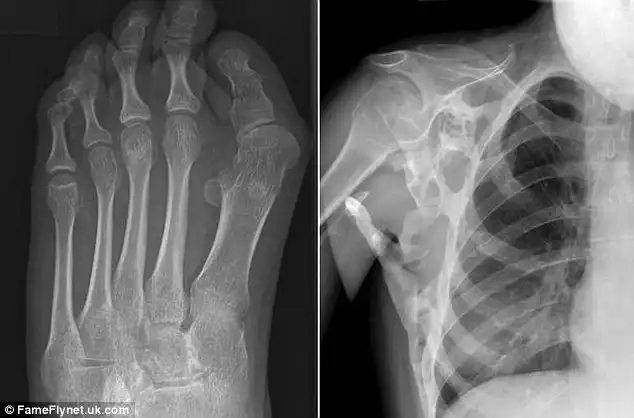

17-летняя девушка из Западного Лондона страдает от прогрессирующей оссифицирующей фибродисплазии (ПОФ) — болезни, которая превращает ее мышцы и сухожилия в кости. Из-за того, что в плече у Шони выросла дополнительная кость, девушка не может поднять руки выше талии. Она даже не в состоянии самостоятельно почистить зубы, помыть волосы или одеть платье, а для того, чтобы сделать прическу, Шони приходится использовать специальные щипцы и расческу с удлиненной ручкой. При этом ее состояние может стать еще хуже.

Малейшее постукивание или удар вызывает у Шони болезненные вспышки, которые становятся причиной необратимого роста костей, которые замещают суставы. Девушке нельзя также делать уколы, так как любая инъекция или биопсия может стать причиной нежелательного роста костей.